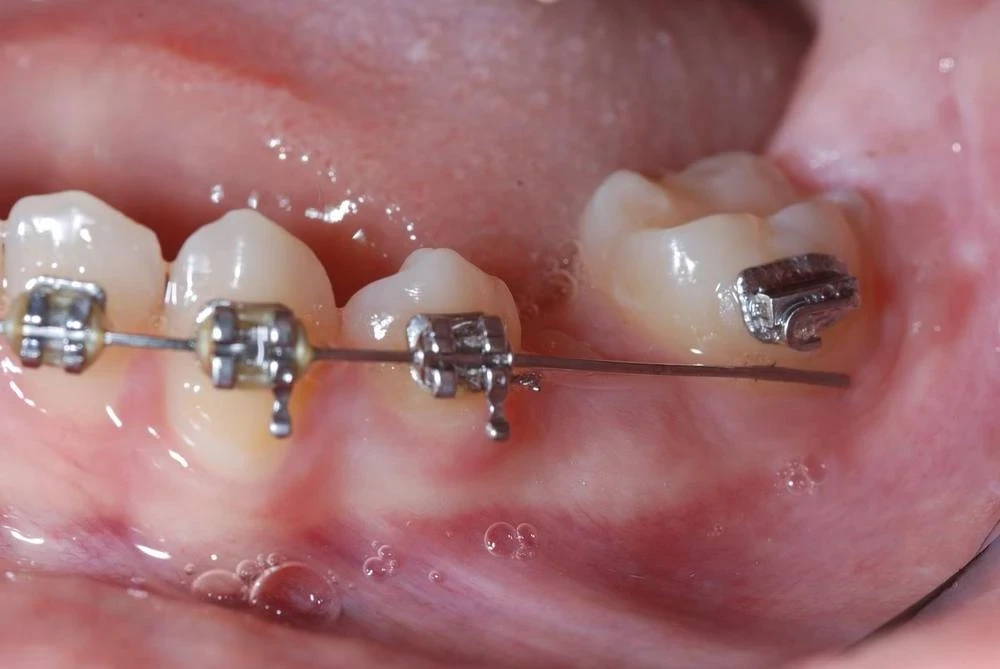

L'orthodontie pré-prothétique

Pourquoi ne pas envisager l’orthodontie préprothétique, dans certains cas, avant de recourir aux autres types de traitements orthodontiques ?

Les reconstructions prothétiques ou implantaires obéissent à certains critères : espace suffisant pour les dents artificielles, parallélisme relatif des racines dentaires, répartition satisfaisante des espaces, absence d’égression de dents antagonistes vers les sites édentés, occlusion correcte, etc.

Si ces critères ne sont pas réunis, le projet prothétique ne pourra palier les défauts que jusqu’à un certain point. La restauration prothétique pourrait même s’avérer impossible ou nécessiter une taille des dents plus importante que prévue.

Ainsi, lorsque certaines anomalies d’occlusion induisent le risque de complexifier la réalisation prothétique, voire de la rendre impossible, la première phase de traitement orthodontique pré-prothétique aura pour objectif de faciliter la phase prothétique ou de la rendre réalisable.

Les objectifs :

Faciliter ou permettre la réalisation de la prothèse en redressant l’axe de la molaire mésioversée, par la correction d’une égression iatrogène (dent qui monte, ou qui descend selon la localisation).

Répartir correctement les espaces entre les dents.

Éviter la prothèse, notamment après l’extraction d’une dent, en refermant l’espace créé par le déplacement orthodontique.